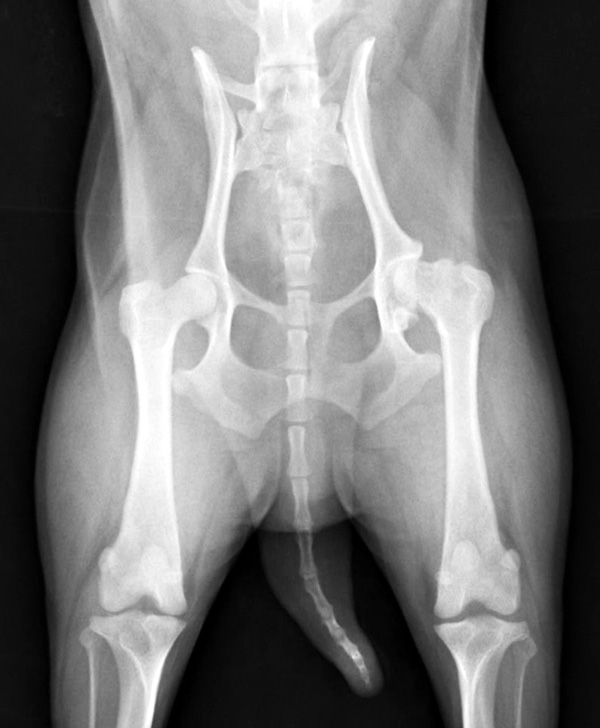

1歳未満の小型犬に多い病気です。成長期に大腿骨頭の血流が悪くなり壊死してしまう病気で、骨が変形して関節炎を起こします。これによって痛みが生じ、悪い方の後肢を上げがちになり、症状が進むと腿の筋肉が萎縮して3本足で歩行するようになります。痛みや跛行のあるものでは手術による早期治療が回復を早めるために重要です。当院では他院からのご紹介などもあり、この手術はとても多く、特にトイプードルが多いです。今回の子も無事元気に走れるようになりました。良かったね。